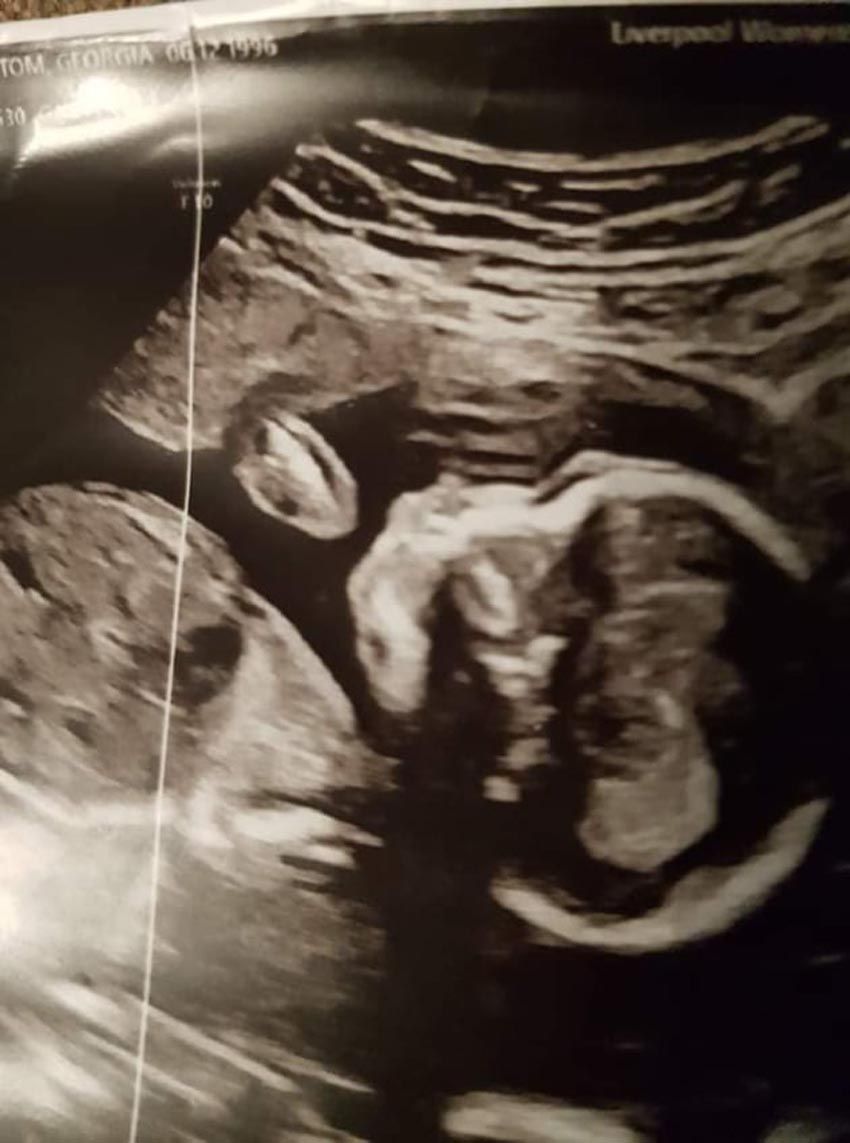

Following her devastating loss, when she and her chef partner, Adam Gray, 29, discovered they were expecting in July last year, they felt blessed – but discovered during a scan in November that their daughter, who they have called Miraya, has hypoplastic left heart syndrome (HLHS).

This means Georgia, who does not work, of Fleetwood, Lancashire, England, faces losing a second baby within days of her being born, as the left side of her heart has not developed properly and her only hope of survival will come from three open heart operations – starting within her first week of life.

Georgia recalled: “I was really worried. I had two ultrasounds, then they sat us down and told us that she had a rare congenital heart defect called HPLS.

“It means she is missing critical portions of the left side of her heart, so it cannot effectively pump blood around the rest of her body.

Told Miraya's only chance of survival would come from three high risk open heart operations, known as the Norwood Procedure – one within a week of her being born, the second at three to five months old and the third at three or four years old – the couple were shell-shocked.